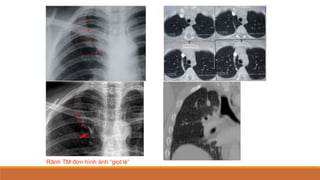

Các rãnh phụ màngphổi

Tần suất gặp cao 



thấp: rãnh phụ dưới

(10-20%), rãnh liên thùy

bé (T) (2%), rãnh tĩnh

mạch đơn (0.4%), rãnh

phụ trên,

Rãnh TM đơn hình ảnh “giọt lệ”

Các rãnh phụmàngphổi Tần suất gặp cao   thấp: rãnh phụ dưới (10-20%), rãnh liên thùy bé (T) (2%), rãnh tĩnh mạch đơn (0.4%), rãnh phụ trên,

• 46.

Rãnh TM đơnhình ảnh “giọt lệ”